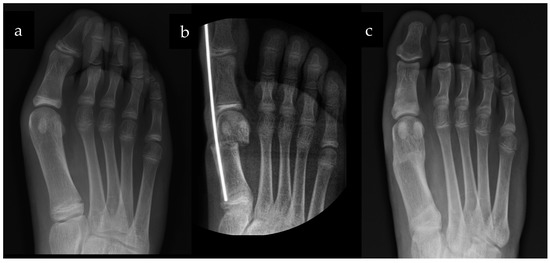

The Minimally Invasive SERI Osteotomy for Pediatric Hallux Valgus

2. Materials and Methods

3.2. Radiological Results